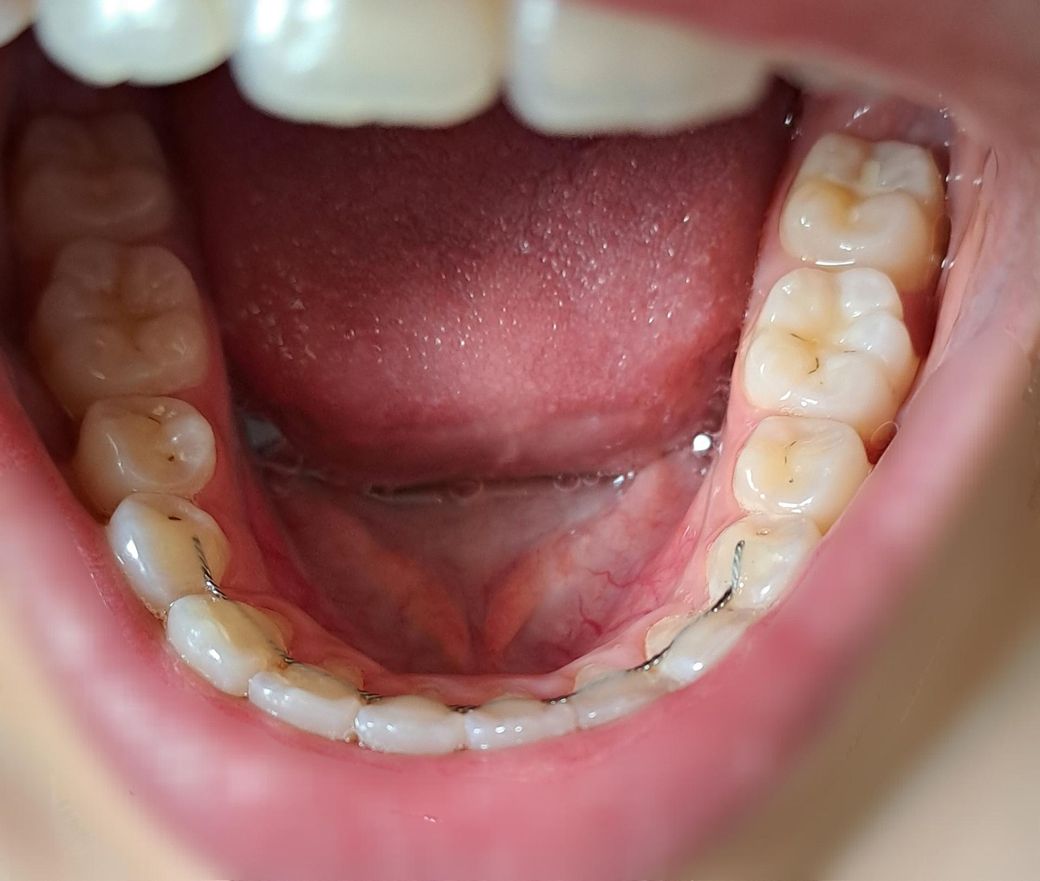

이거 충치일까요? 아니라면 무엇일까요

이빨 사이사이에 있는 검은 점이요..

아무리 봐도 충치 같은데 1년 전 부터 있었거든요

치과는 가야지 가야지 하다가 안 갔었는데 1년이나 지난거면 충치는 아닌거 같기도 하고.. 그럼 뭘까요?

충치도 있고 변색도 있는 것 같습니다. 다만, 진행이 빠르게 되는 것은 아닌 정지성 우식(충치)으로 보여집니다. 이전에 레진 충전했던 흔적도 보이는데 레진 재료에 떼가 꼈다고 보시면 됩니다. 아프지 않으면 그냥 둡니다.

정지우식으로 보여집니다. 멈추었던 우식이 다시 진행할수 있으니 정기검진과 치아관리를 잘 하면 좋을것 같습니다. 건강하세요.

사진으로 보이는 부위는 충치일 수도 있지만 간단한 착색일 수도 있습니다. 충치인지 착색인지 확인을 하기 위해서는 치과에서 진료를 받아보는 것이 좋습니다.